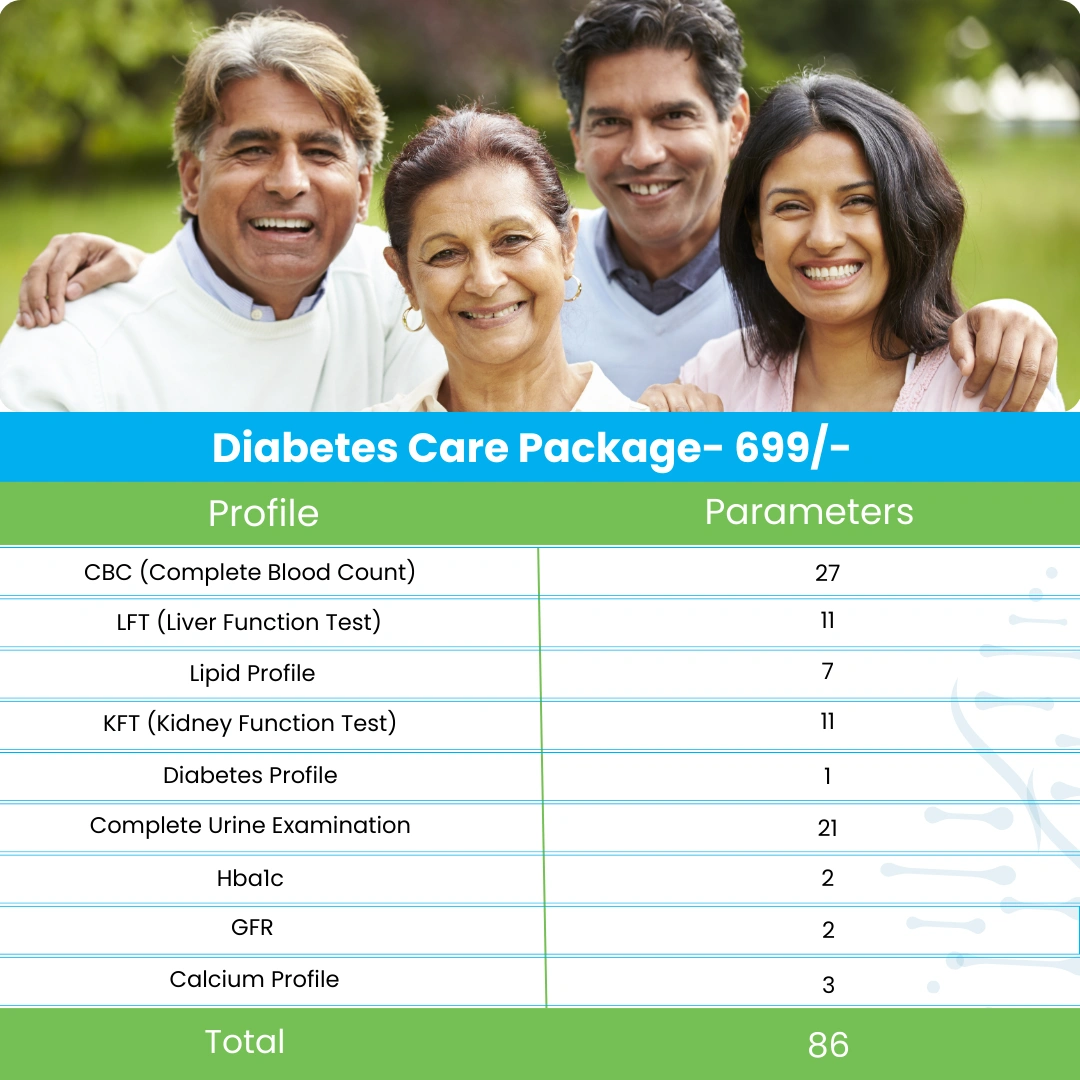

Packages

Packages